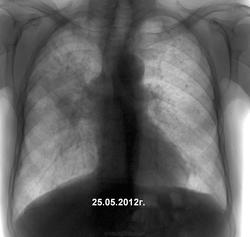

Второй, с фиброзной каверной за правым корнем и диссеминацией в верхних долях, несколько задержался к фтизиатру.

во втором случае мне видится инфильтрация "с распадом". Скорее пневмоническая, но дообследование ПТД показано.

Повторюсь, архива нет (не спорю, было бы интересней и легче). Первый бомжеватого вида, жалобы на кашель. Написал предположительно центральный рак в/дол. бронха с ателектазом доли, направил на КТ, консультацию онколога. Думаю не только на лечение, но и на КТ бабла не соберет. Второй - то ли дядя, то ли знакомый коллеги, живет в селе, то же без архива. Стажа в шахте не уточнил, но, хоть и видя очаговые изменения в легких, предположил опухоль в В3, направил на КТ. Тут пообещали результаты принести. Выложу.

Это второго, который шахтер с 20 летним стажем.

На первое место - силико-туберкулёз